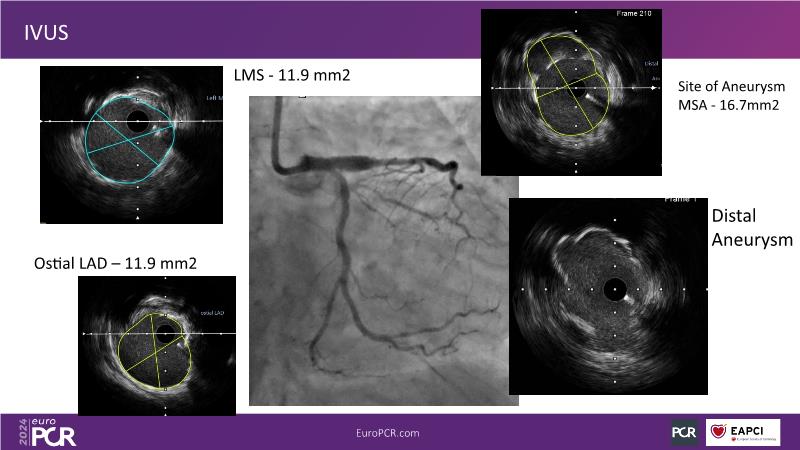

From innovation to reality: the impact of Cre8 EVO technology on complex PCI

This session is a good opportunity to delve into the contemporary technical and clinical complexities surrounding complex PCIs in challenging patient cases. Explore the necessary tools and treatment strategies to enhance peri-procedural and long-term clinical outcomes, and follow discussions on the unique technologies of Cre8 EVO in complex PCI scenarios.